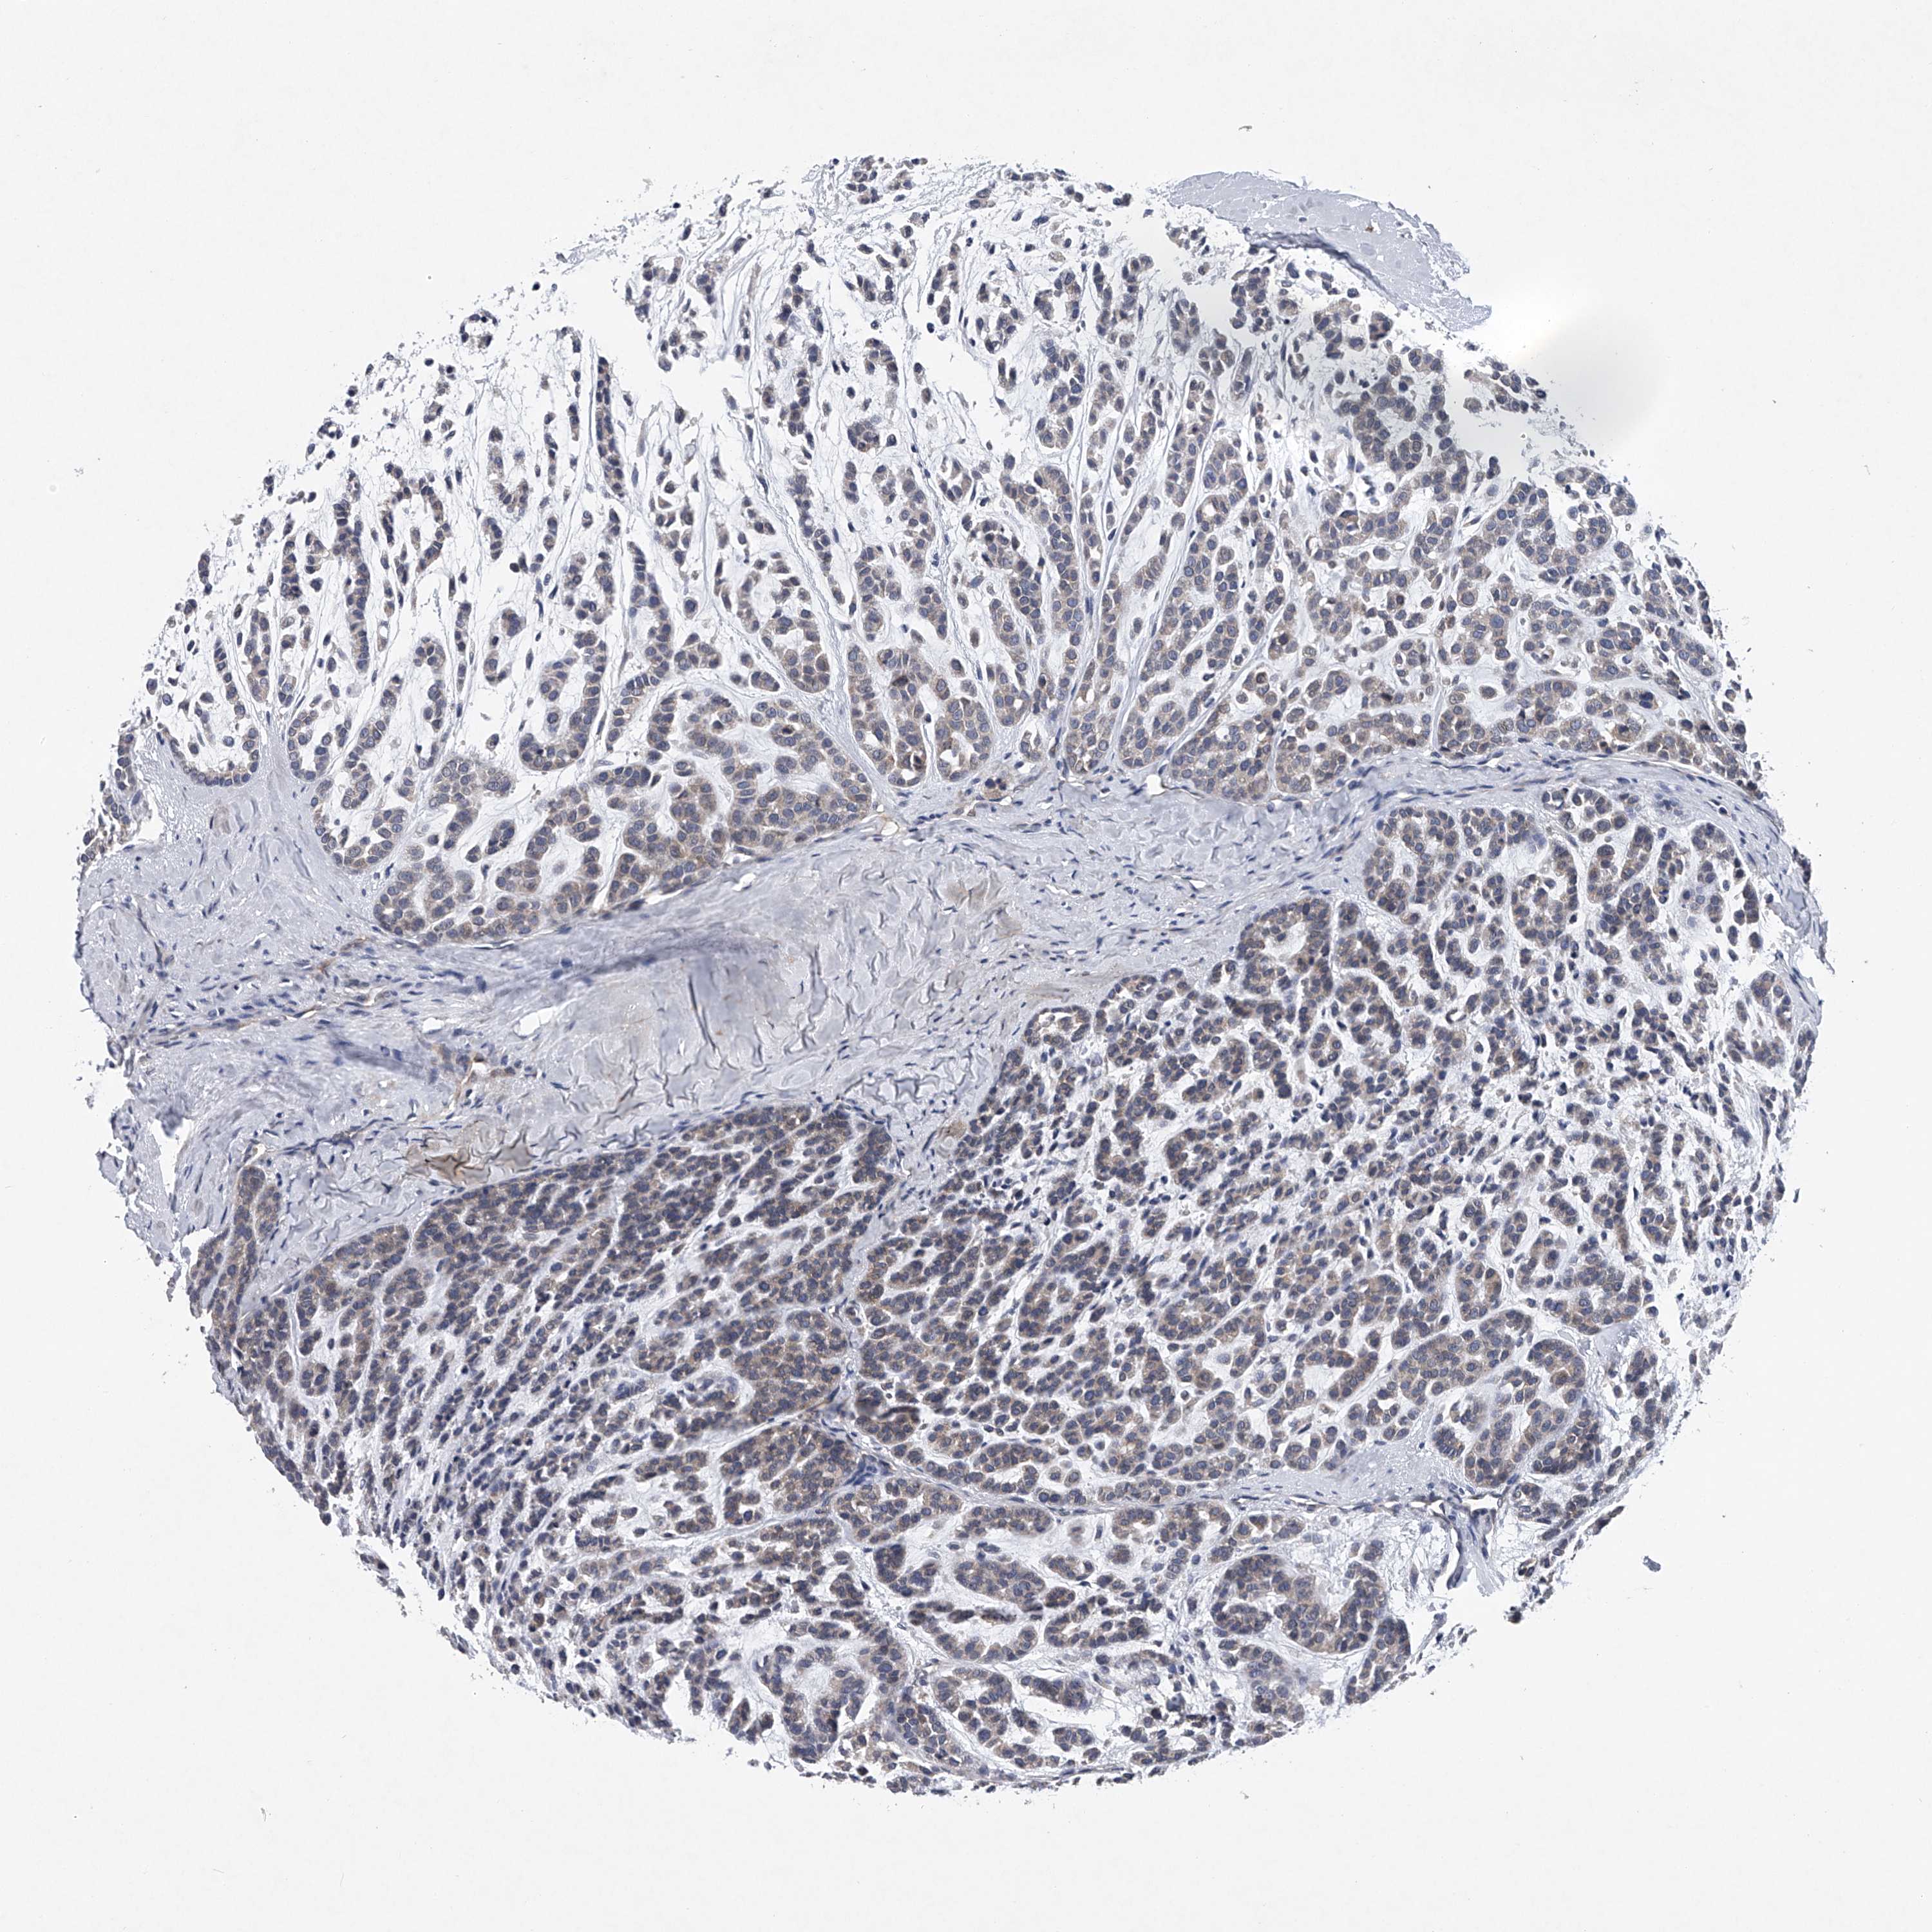

HEAD AND NECK CANCER - Protein expressioni

A mouse-over function shows sample information and annotation data. Click on an image to view it in a full screen mode. Samples can be filtered based on level of antibody staining by selecting one or several of the following categories: high, medium, low and not detected. The assay and annotation is described here.

Antibody stainingi

Antibody staining in the annotated cell types in the current human tissue is reported as not detected, low, medium, or high, based on conventional immunohistochemistry profiling in selected tissues. This score is based on the combination of the staining intensity and fraction of stained cells.

Each image is clickable and will lead to virtual microscopy that enables deeper exploration of all samples and also displays staining intensity scores, fraction scores and subcellular localization as well as patient and tissue information for each sample.

Antibody CAB034107

Staining

High

Medium

Low

Not detected

Intensity

Strong

Moderate

Weak

Negative

Quantity

>75%

75%-25%

<25%

None

Location

Nuclear

Cytoplasmic/membranous

Cytoplasmic/membranous,nuclear

Squamous cell carcinoma, NOS